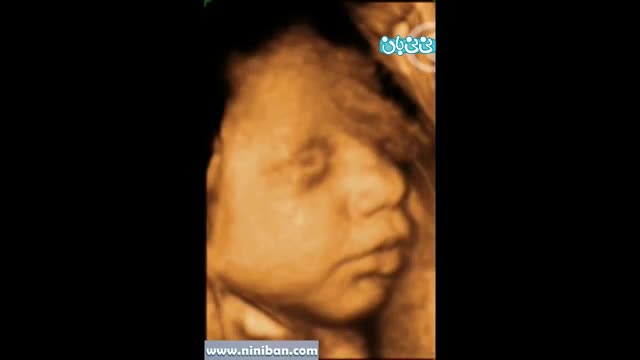

سونوگرافی چهار بعدی در بارداری هفته سی و دوم

۴ سال پیش

77394 بازدید